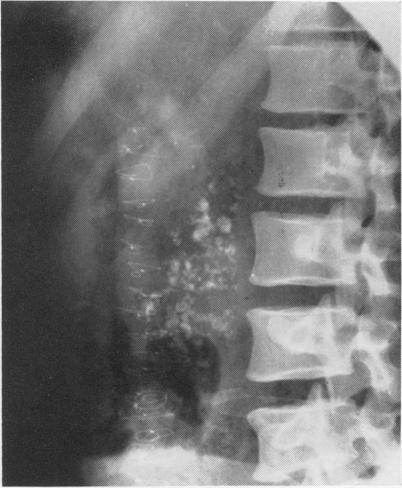

HOWARD J M, EHRLICH E W

Ann Surg. 1960 Jul;152(1):135-46. doi: 10.1097/00000658-196007000-00019.